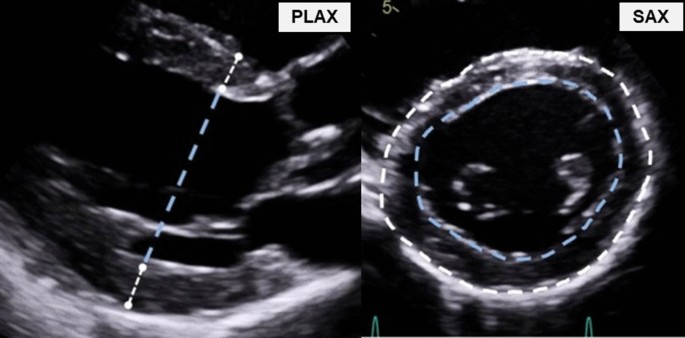

Measure the PWT SWT and LVID. It is commonly used and has been. Web LV Mass Calculator Overview.

The optimal view is the mid transgastric LVSAX view. Web LVM was calculated by summing the short axis slice volumes at end-diastole. LVMI is calculated using the following equations.

Web PHM Left ventricular mass Right ventricular mass. Web LV mass calculated by the 2D volumetric method was less compared with PLA and PSA methods 3164 vs 3390 vs 3551 gm 27. Obtain the LVSAX view in Diastole.